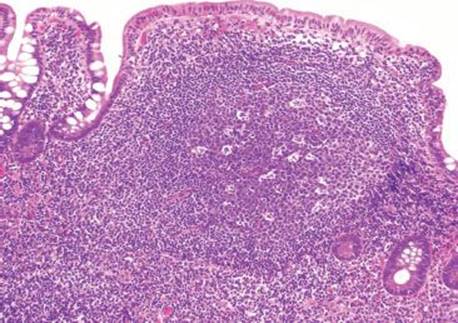

Answer: You are not alone! Prominent lymphoid aggregates can be especially alarming in the terminal ileum and, thus, are a common source of consultation. The small bowel serves as an essential component of the immune system through its perpetual surveillance of the passing luminal contents. Diligent immunosurveillance is facilitated through specialized epithelial cells (M-cells) that transport luminal antigens to the lymphoid aggregates (designated “Peyer patches” when seen in the terminal ileum). Hyperplastic lymphoid aggregates can be sufficiently large as to be visualized endoscopically and can also serve as intussusception lead points, especially in young children.5,6 The epicenter of lymphoid aggregates is in the mucosa but especially prominent cases can feature extension into the submucosa, raising concerns for a hematolymphoid malignancy. Histologic features reassuring for a benign, reactive process include the presence of germinal centers, tingible body macrophages, and a polymorphous constituent lymphoid population (i.e., a variety of cell sizes represented); however if the focus in question seems at all concerning, a quick immunohistochemical panel may be worthwhile (Figs. 3.19–3.37) (Table 3.1).

Figure 3.20 Normal terminal ileum. The overlying villi of the terminal ileum are characteristically shorter than those seen in the duodenum and jejunum (Figs. 3.3 and 3.13). At low power, the prominent lymphoid aggregate is seen confined within the mucosa (arrowheads highlight the narrow wisp of muscularis mucosae). Although the crypts are not identical copies of each other (the crypts are variably sized with varying amounts of intervening lamina propria), these slight differences are due to the prominent lymphoid aggregate and are entirely within the spectrum of normal terminal ileum histology. The lymphoid aggregate gently pushes the crypts apart; there is neither acute inflammation actively destroying the epithelium nor features of chronic injury (such as pyloric gland metaplasia). As a result, the superficial epithelium could be theoretically pulled off the lymphoid aggregate since there is no destructive inflammatory injury tethering the epithelium to the lymphoid aggregate. See figures 3.64, 3.66–3.70 to contrast this normal architecture with features of established active chronic injury.